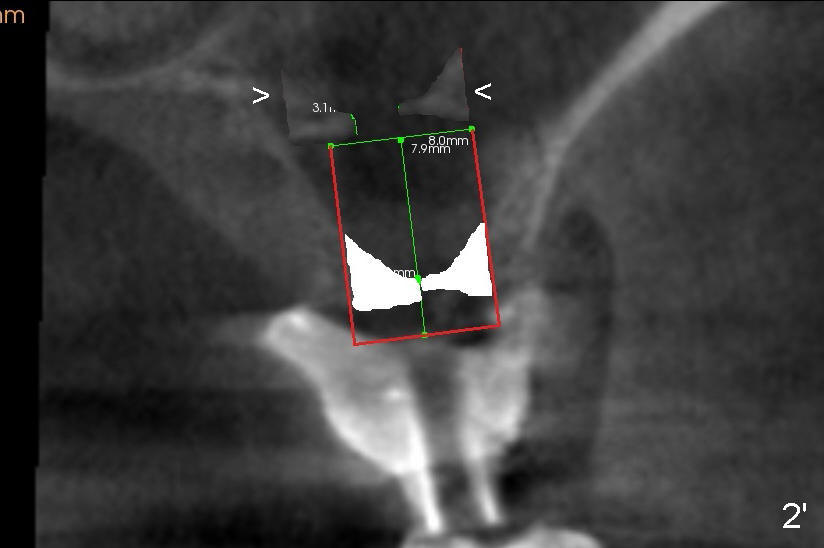

Fig.2: CBCT coronal section of the edentulous area of #14 (surgical stent for CT scan). The red boxed area represents a 8x11 Tatum screw implant to be engaged into both the buccal (B) and lingual (L) walls of the concave sinus floor for primary stability.

Fig.2' simulates sinus lift (<).